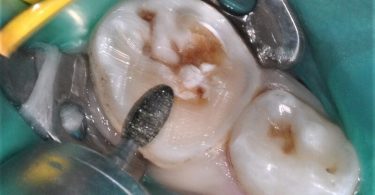

Após a anestesia e a colocação do isolamento absoluto com dique de borracha (fig. 5) foi iniciado o preparo dentário para a colocação de uma coroa de zircónia pré-formada, seguindo as instruções do fabricante. Inicialmente, foi realizada uma redução da superfície oclusal de 1-2 mm, seguindo o contorno oclusal, com uma broca em chama de vela diamantada (fig. 6). De seguida, foi efetuada uma redução supragengival de todas as paredes dentárias com uma inclinação ligeiramente convergente para oclusal. Foram eliminados os contactos interproximais e toda a coroa clínica foi reduzida em cerca de 20-30%, seguido de um cuidadoso desgaste com uma broca em fio de faca diamantada da margem da preparação, cerca de 1-2 mm infragengival, para eliminar todas as margens ou degraus. Todas as linhas de ângulo foram ligeiramente arredondadas (fig. 7).